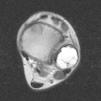

Ante tal hallazgo se derivó a la paciente a Traumatología Infantil que solicitó resonancia magnética (figs. 2 y 3) que mostró niveles de contenido líquido compatibles con un quiste óseo aneurismático. Se procedió a punción-aspiración que resultó negativa para células malignas y con anatomía patológica compatible con quiste óseo aneurismático. La paciente sigue controles evolutivos para valorar posible tratamiento quirúrgico en un futuro.